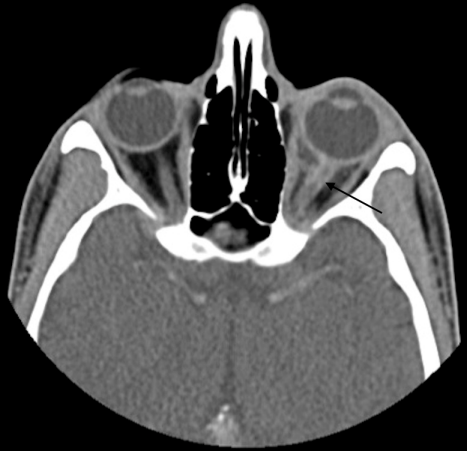

A 29-year-old Hispanic male presented with a week of blurriness in his left eye that progressed to complete vision loss. He was HIV positive for 6 years with a latest CD4 count of 100 and a viral load of 617 copies/mL on HAART therapy. He noted fevers and chills, but no other symptoms. On examination, the left pupil was fixed with no response to light. A reverse relative afferent pupillary defect was present in the right eye. The left optic nerve was edematous with blurring of margins. A CT scan showed enhancement of the retrobulbar optic nerve of the left eye with an adjacent, discrete soft tissue enhancement bordering the posterior globe (Figure 1 [Fig. 1]). Two weeks later, an MRI showed diffuse thickening and contrast enhancement involving the retrobulbar portion of the left optic nerve associated with a surrounding soft tissue lesion within the intraconal orbital fat, and the lesion seemed to be extending more posteriorly than the previous CT image (Figure 2 [Fig. 2]). The mass abutted the posterior aspect of the sclera. The lesion demonstrated low T1 and intermediate T2 signal intensities and heterogeneous contrast enhancement. There was also nodular contrast enhancement of the left optic nerve disc. The size of the lesion measured 17.4 mm x 15 mm x 10.6 mm. Cerebrospinal fluid studies were unremarkable. An anterior orbitotomy with exploration and biopsy of the left orbital mass was performed.